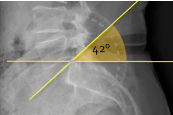

Q what is the name of this measurement? and what is the average + range?

A: Lumbosacral Angle

assesses the angle of the sacrum relative to a horizontal line. The average is 41°, with a range of 26-57°.